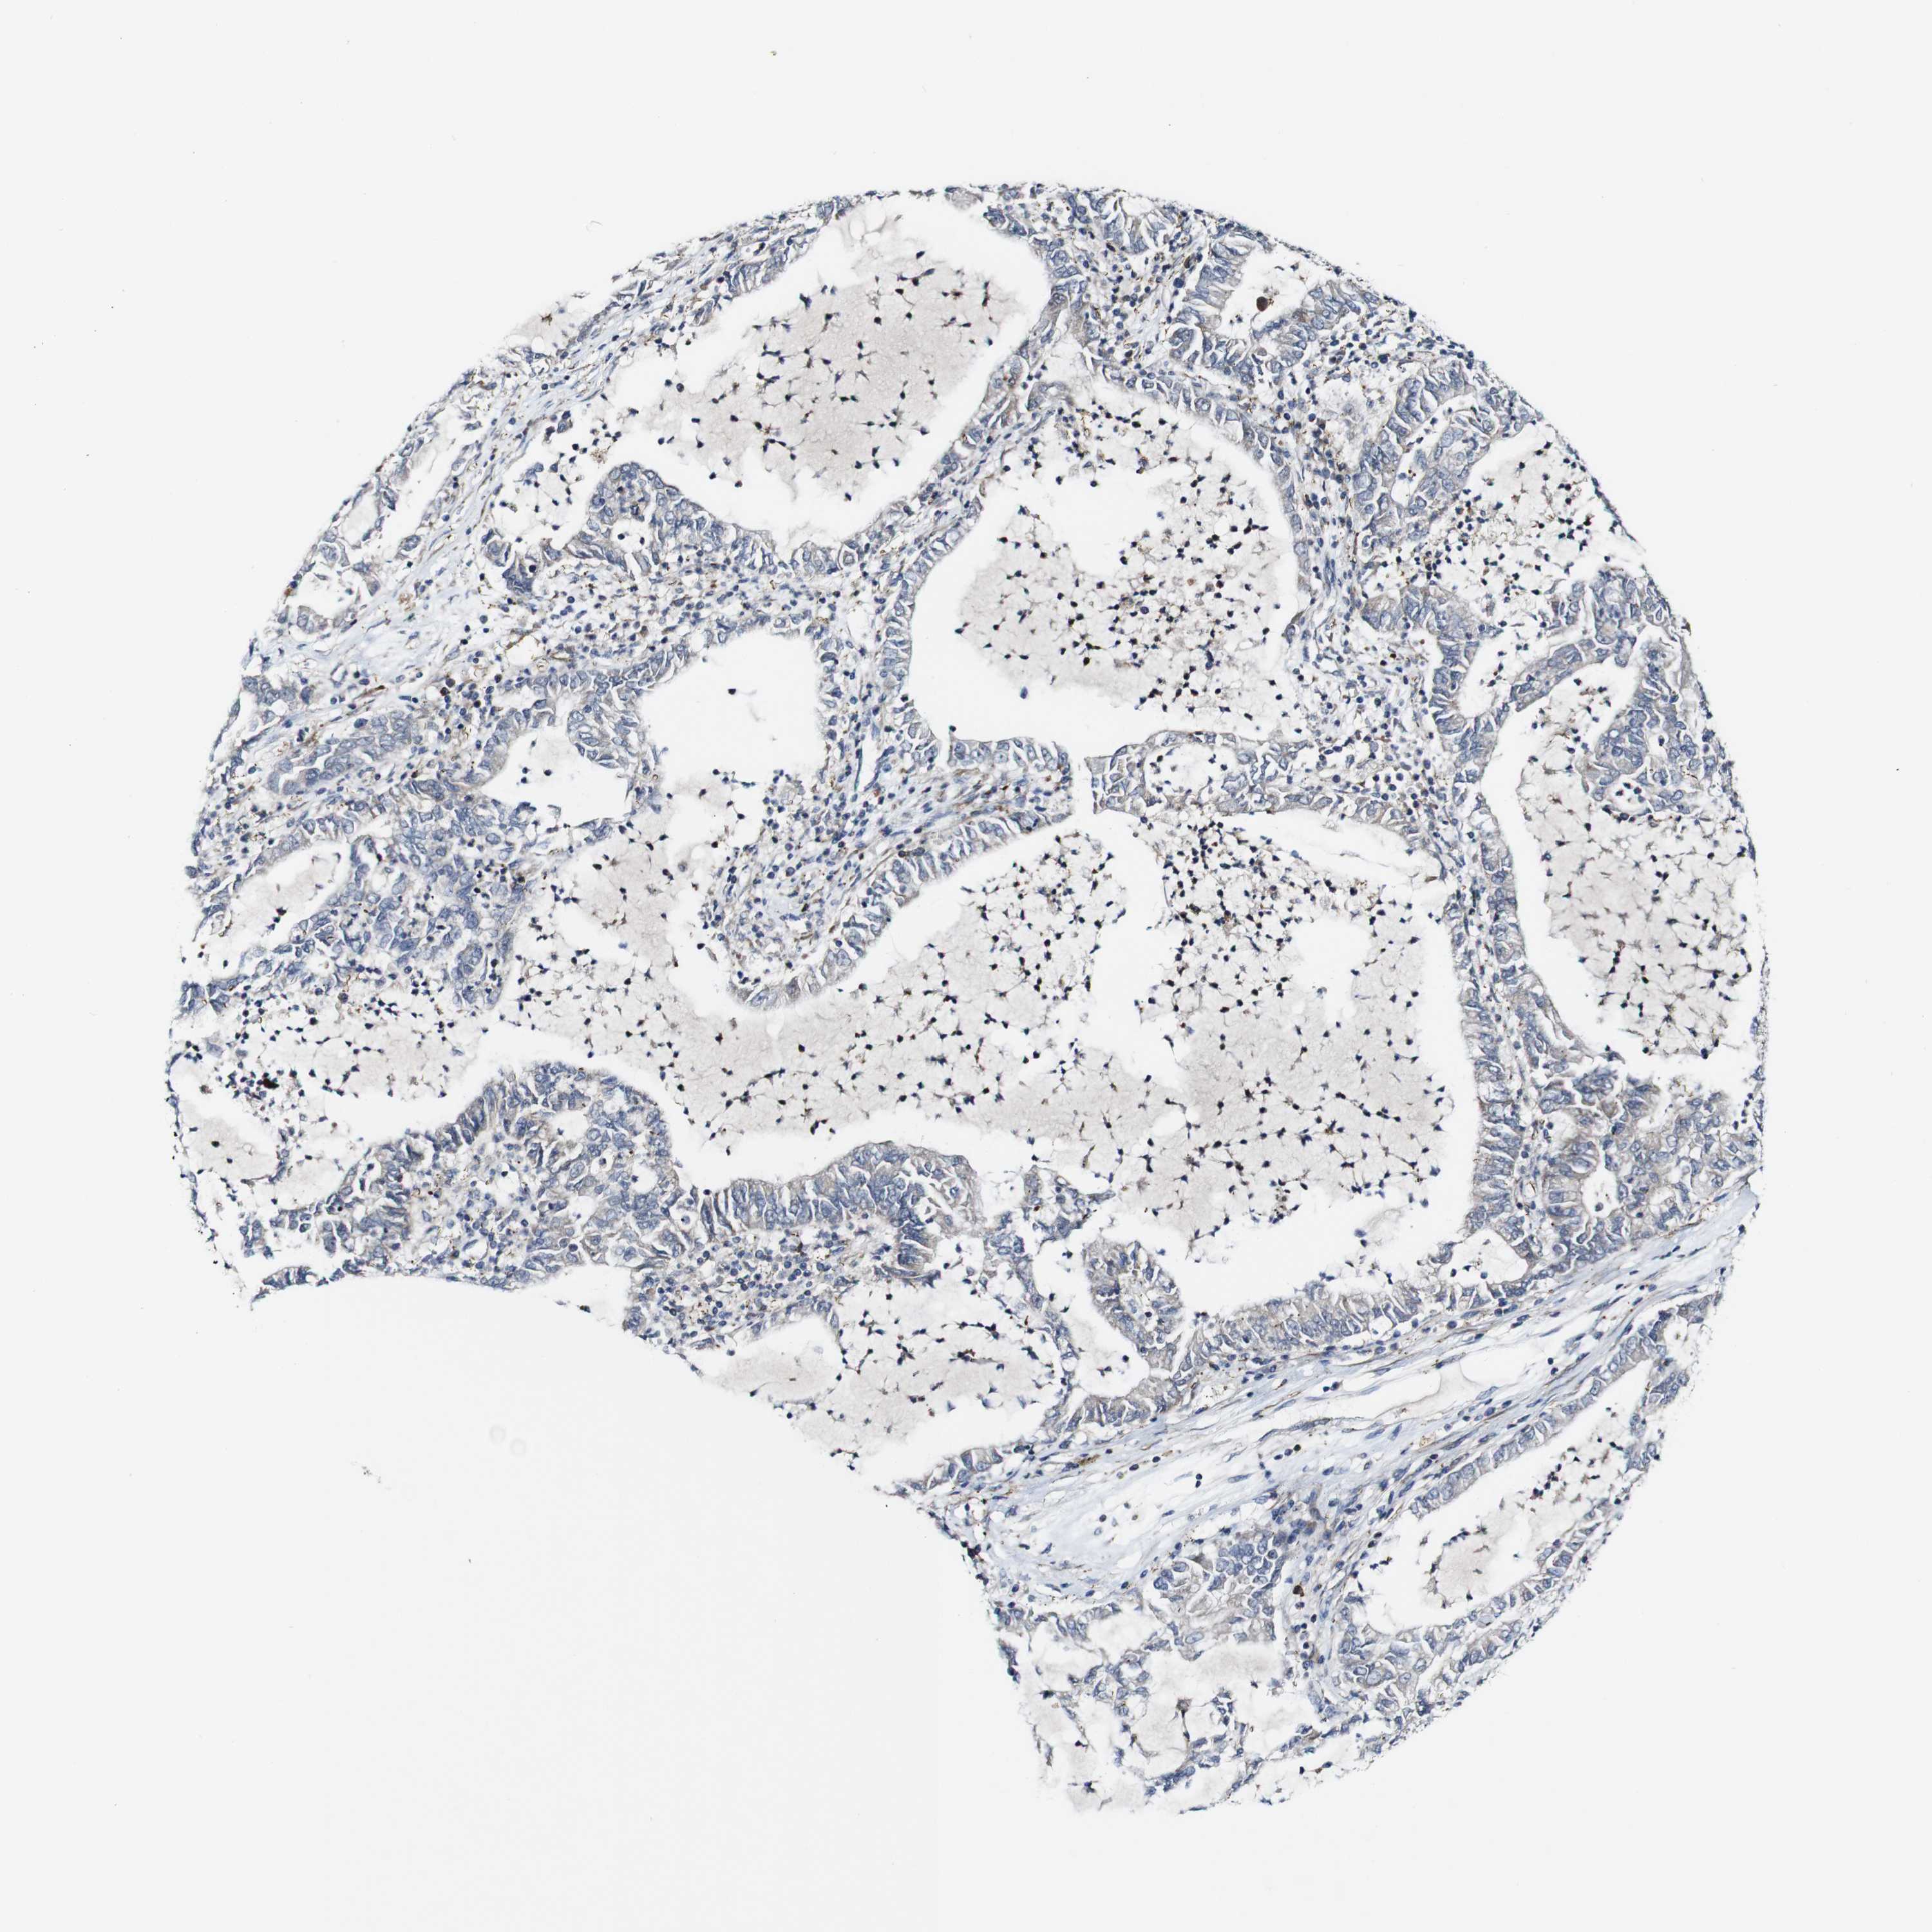

LUNG ADENOCARCINOMA (VALIDATION) - Interactive survival scatter ploti

The Survival Scatter plot shows the clinical status (i.e. dead or alive) for all individuals in the patient cohort, based on the same data that underlies the corresponding Kaplan-Meier plots. Patients that are alive at last time for follow-up are shown in blue and patients who have died during the study are shown in red.

The x-axis shows the expression levels (FPKM) of the investigated gene in the tumor tissue at the time of diagnosis. The y-axis shows the follow-up time after diagnosis (years). Both axes are complimented with kernel density curves demonstrating the data density over the axes. The top density plot shows the expression levels (FPKM) distribution among dead (red) and alive patients (blue). The right density plot shows the data density of the survived years of dead patients with high and low expression levels respectively, stratified using the cutoff indicated by the vertical dashed line through the Survival Scatter plot. This cutoff is automatically defined based on the FPKM cutoff that minimizes the p-score. The cutoff can be changed by dragging the vertical line or by entering a cutoff value in the square labeled "Current cut-off".

Under the Survival Scatter plot the p-score landscape (black curve; left axis) is shown together with dead median separation (red curve; right axis). Dead median separation is the difference in median mRNA expression between patients who have died with high and low expression, respectively. It is calculated as follows: median FPKM expression of dead patients with high expression - median FPKM expression of dead patients with low expression. This is intended to aid the user in visually exploring custom cutoffs and the associated p-scores and dead median separation.

Individual patient data is displayed and can be filtered by clicking on one or more of the category buttons on the top of the page. Categories describing expression level and patient information include: high, low, alive, dead, female, male and tumor stages. The scale of the x-axis can be toggled between linear and log-scale by clicking on the "x log" button. Mouse-over function shows TCGA ID, patient information and mRNA expression (FPKM) for each patient.

& Survival analysisi

Kaplan-Meier plots summarize results from analysis of correlation between mRNA expression level and patient survival. Patients were divided based on level of expression into one of the two groups "low" (under cut off) or "high" (over cut off). X-axis shows time for survival (years) and y-axis shows the probability of survival, where 1.0 corresponds to 100 percent.

JAK2 is not prognostic in Lung Adenocarcinoma (validation)

: 7.33

Average pTPM 10.9

Number of samples 105